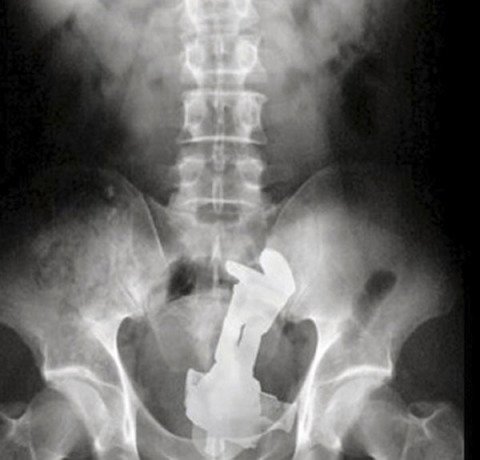

座ったらうっかり肛門にバズ・ライトイヤーが入ってしまいまして…

座った所にたまたま逆立ちしたバズが…?

そっちからか〜

中で羽出てるのがヤバい

羽広げたのがダメだったのかな